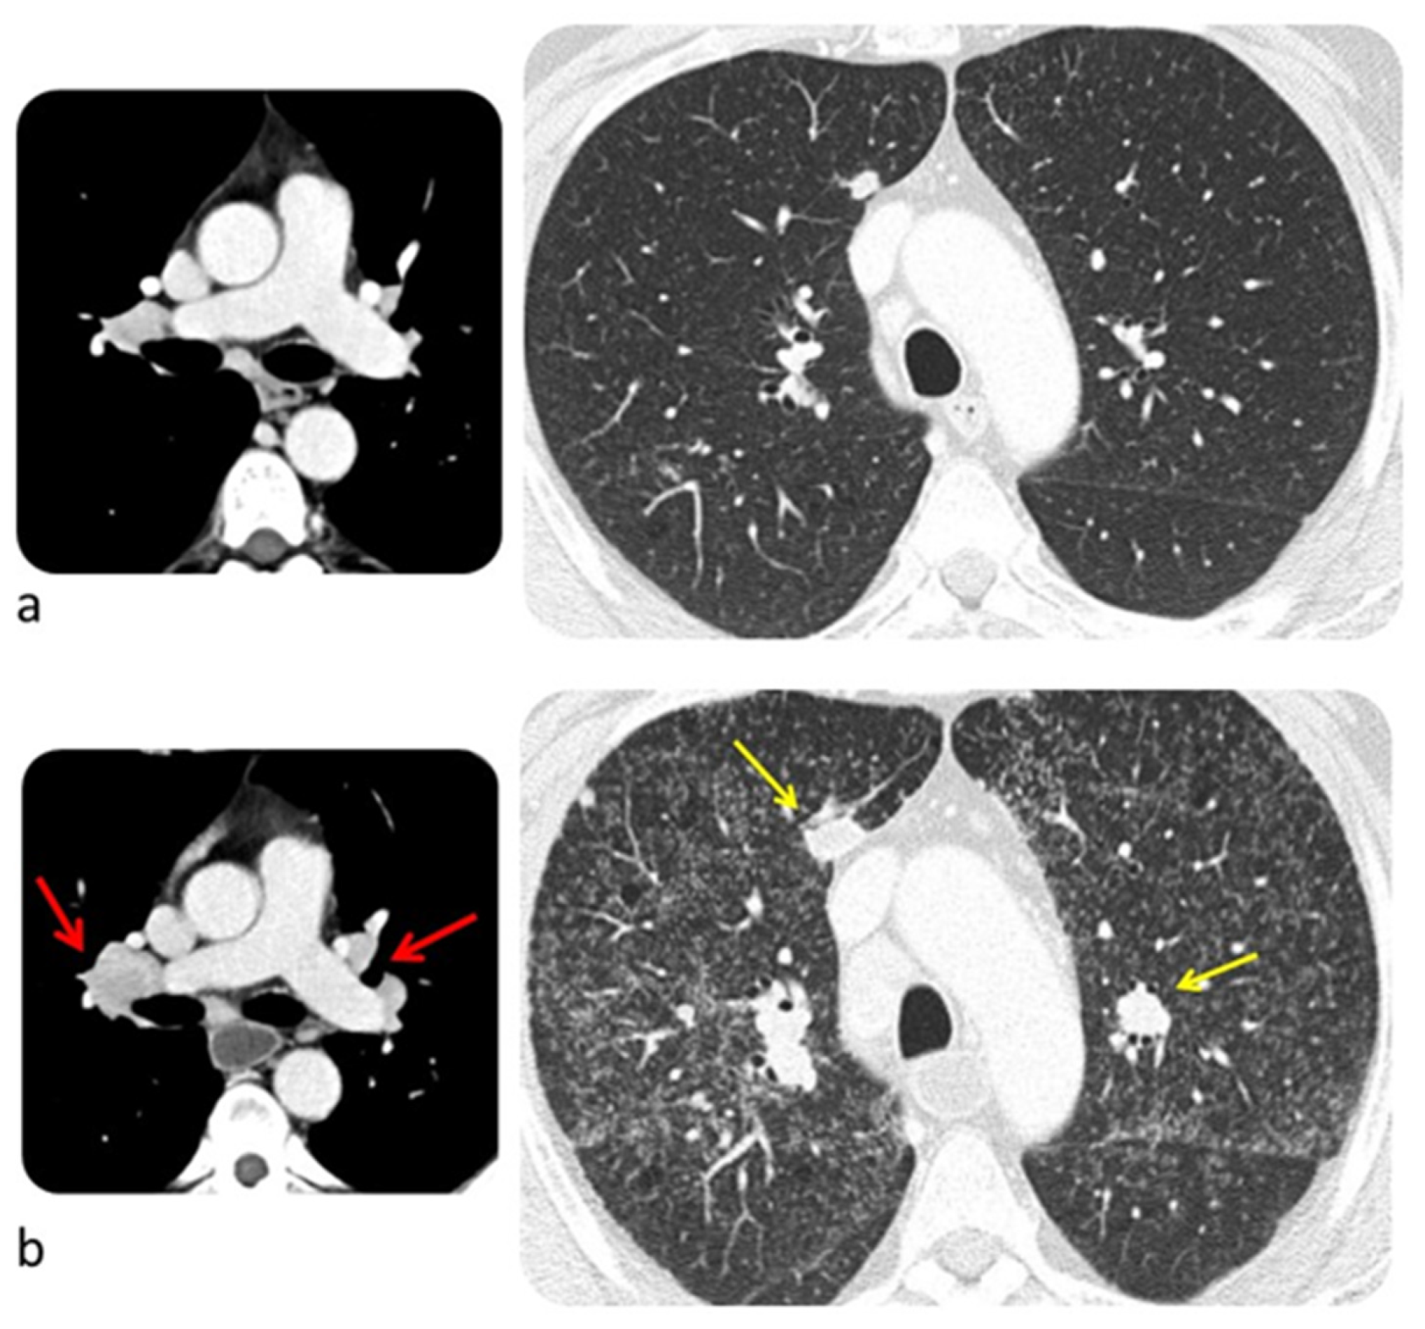

6.3. Lung

8.2. Cardiac Toxicity